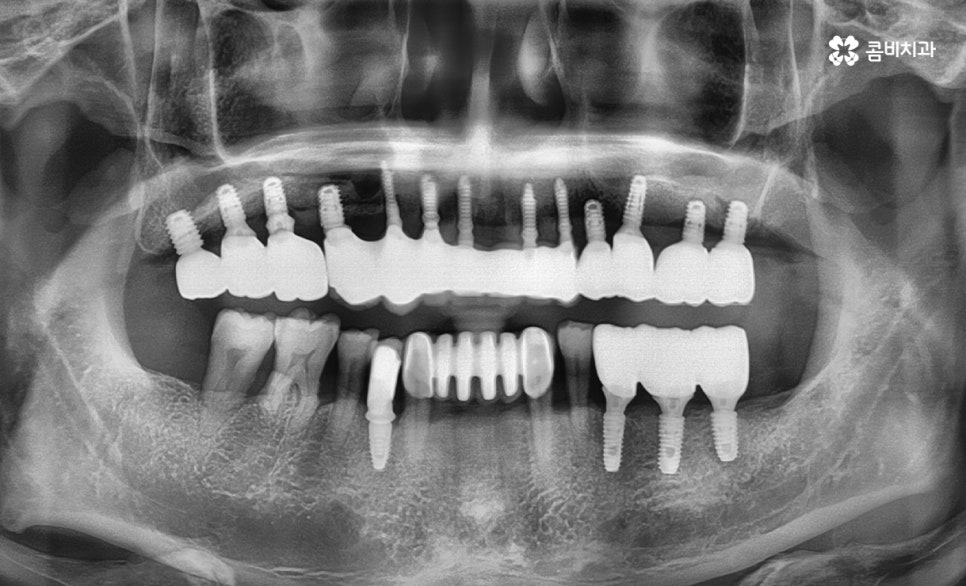

상악동 거상술이 병행되어 치료가 완료된 모습

그리고 많은 분들께서 임플란트를 하신 후에 보통 10년 이상은

문제없이 사용이 가능하다고 알고 계시지만

어떻게 관리를 하냐에 따라서 반영구적인 사용도 가능하고

반대로 부작용을 겪거나 재수술을 하는 사례도 있는 만큼

진료에 대한 올바른 이해와 담당의와의 소통 그리고

주기적인 검진을 통해서 보다 건강한 유지관리가 필요합니다.